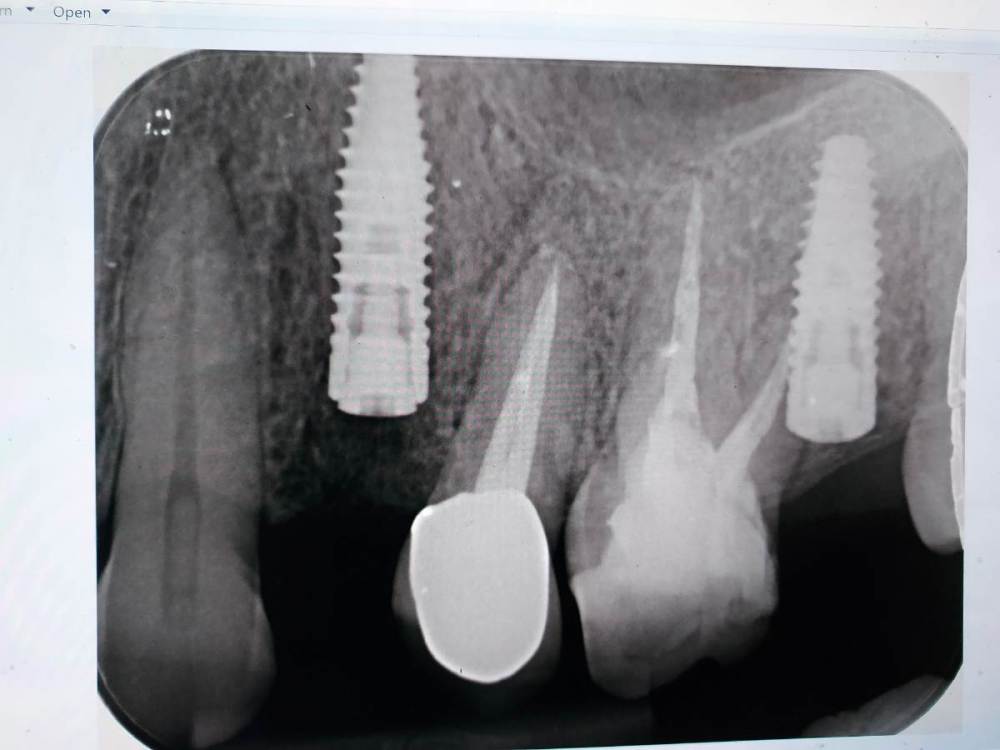

lola-1234 Опубликовано 7 октября, 2021 Автор Поделиться Опубликовано 7 октября, 2021 (изменено) В пятницу сделали новый снимок имплантов. У меня не получается доктора убедить достать имплант. Он считает, что все нормально и уже 26го октября можно ставить формировать. Каждый раз объясняет причины того, что болит зуб,чем-то новым. Похоже он сам не знает. Сказал, что возможно заглушка у импланта на месте четвёртого зуба выкрутилась, это видно даже на снимке.Это вызывает воспаление. Мол как только заглушку он вынет, и вкрутит формировать боли пройдут. Мол 95 процентов все будет хорошо. А у меня надкостница вся от зуба болит, я уже сама лёд к зубу приложила, не чувствует уже ничего ? Я незнаю, может мне к другому хирургу идти и доставать имплант? Или уже поздно? Или всё же нужно своему хирургу довериться? Изменено 7 октября, 2021 пользователем lola-1234 Ссылка на комментарий

Irouil Опубликовано 7 октября, 2021 Поделиться Опубликовано 7 октября, 2021 На снимках явных проблем не видно Вы до сих пор предпочитали терпеть дискомфорт и/или боли, прошло уже целых 3 месяца. Скорее всего, за оставшиеся несколько недель ничего необратимого уже не произойдёт Ссылка на комментарий

lola-1234 Опубликовано 28 октября, 2021 Автор Поделиться Опубликовано 28 октября, 2021 (изменено) Снова пишу вам на форум. Уже не знаю,что делать. Рассказываю. Установили мне формирователи, импланты оба прижились. А вот моя проблемма никуда не делась ? Зуб так и болит, причём дергающая боль по ощущением там где заканчивается кончик корня. На зуб укусить не возможно, больно. Мой хирург не верит, что болит из-за импланта. Говорит,что стоит хорошо, далеко от зуба. Имплант прижился, значит инфекции нет. Кстати как оказалось, зуб ещё живой. Мне опять его протестировали на холод. Видимо я тогда рано запаниковала. Но на снимке возле корня уже видно затемнение. Но что вызвало его воспаление не понятно. Мне врач предлагает удалять нерв. А там посмотрим. Если будет болеть дальше, то тогда выкручивать уже имплант придётся. А если мы выкрутим сначала имплант, а зуб так и будет болеть, то это худший сценарий. А мне так жалко клык. Он же тогда мертвый станет. ? Так и живу с болью, не решаюсь зуб депульпировать. Никто из врачей мне точно не может сказать что делать. Похоже ситуация не стандартная, и врачи сами не знают в чём причина. Изменено 28 октября, 2021 пользователем lola-1234 Ссылка на комментарий